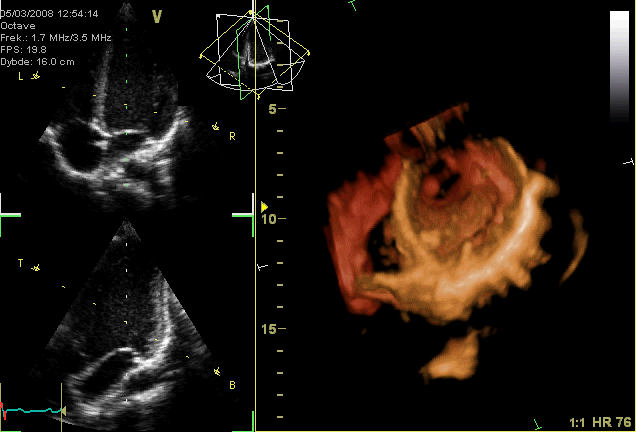

Kalbin atışının üç boyutlu ultrasonografide görünümü

Ad:  Apikal4D.gif

Gösterim: 5048

Boyut:  704.7 KB